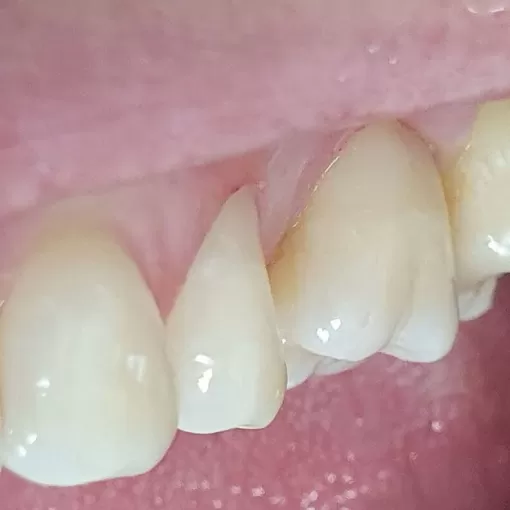

Шиловидный зуб 22

Иногда пациенту необходима помощь до снятия брекет-системы. Шиловидный зуб 22, на время лечения принято решение восстановить композитом, в дальнейшем замена на керамический винир.

Брекет-систему для выполнения работы не снимали. Зуб развёрнут, т.к. восстановлен по оси, которая наклонена. Следующий шаг в лечении - фиксация брекета.